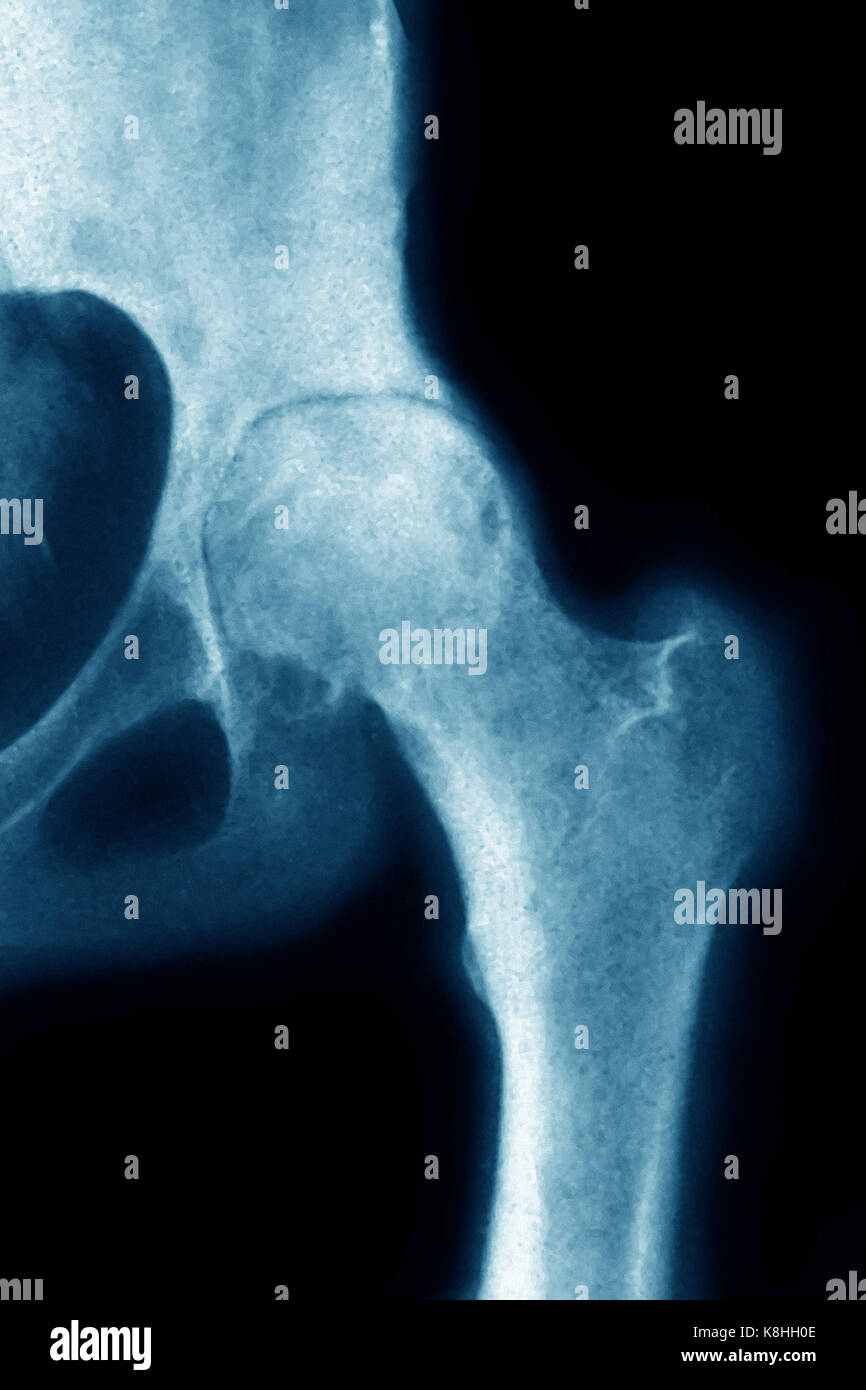

Hip X Ray With Osteoarthritis . A standard hip protocol includes an anteroposterior view. The scoring hip osteoarthritis with mri system evaluates eight mri features, including cartilage damage, subchondral bone marrow lesions, subchondral cysts, labral pathology, joint effusion, loose). Radiography is relatively inexpensive and is widely available. Different grading schemes are described for plain radiographs of the hip: Not much can be done for osteoarthritis of the hip. Radiography is the first line of imaging for hip pain and suspected oa. While it is not “curable”, it. Occasionally, a magnetic resonance imaging (mri) scan or a.

A standard hip protocol includes an anteroposterior view. While it is not “curable”, it. Different grading schemes are described for plain radiographs of the hip: Not much can be done for osteoarthritis of the hip. Radiography is relatively inexpensive and is widely available. Occasionally, a magnetic resonance imaging (mri) scan or a. The scoring hip osteoarthritis with mri system evaluates eight mri features, including cartilage damage, subchondral bone marrow lesions, subchondral cysts, labral pathology, joint effusion, loose). Radiography is the first line of imaging for hip pain and suspected oa.

Hip X Ray With Osteoarthritis The scoring hip osteoarthritis with mri system evaluates eight mri features, including cartilage damage, subchondral bone marrow lesions, subchondral cysts, labral pathology, joint effusion, loose). While it is not “curable”, it. Not much can be done for osteoarthritis of the hip. The scoring hip osteoarthritis with mri system evaluates eight mri features, including cartilage damage, subchondral bone marrow lesions, subchondral cysts, labral pathology, joint effusion, loose). Radiography is the first line of imaging for hip pain and suspected oa. Radiography is relatively inexpensive and is widely available. Different grading schemes are described for plain radiographs of the hip: A standard hip protocol includes an anteroposterior view. Occasionally, a magnetic resonance imaging (mri) scan or a.